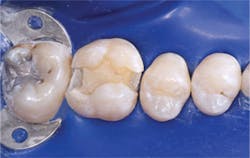

- Place resin-modified glass ionomer on the deepest areas of the tooth preparation, not on the margins. The material should be about 0.5 mm thick or slightly thicker. Cure it.

- Place the self-etch bonding agent of your choice. The bonding brands noted in this article have well-proven excellent results on dentin and enamel without total etching. Although when total-etch is done well it is successful, our research shows it creates significantly more unpredictable postoperative tooth sensitivity than self-etch techniques.

- Place the restorative resin in increments, starting with 0.5 mm in the deepest portion of the box form, increasing to 1.0 mm and finally to 2.0 mm increments. Clinicians Report research has shown that currently popular curing lights do not cure the entire depth of a typical box form at 7 mm.

- Finish and polish the restoration.